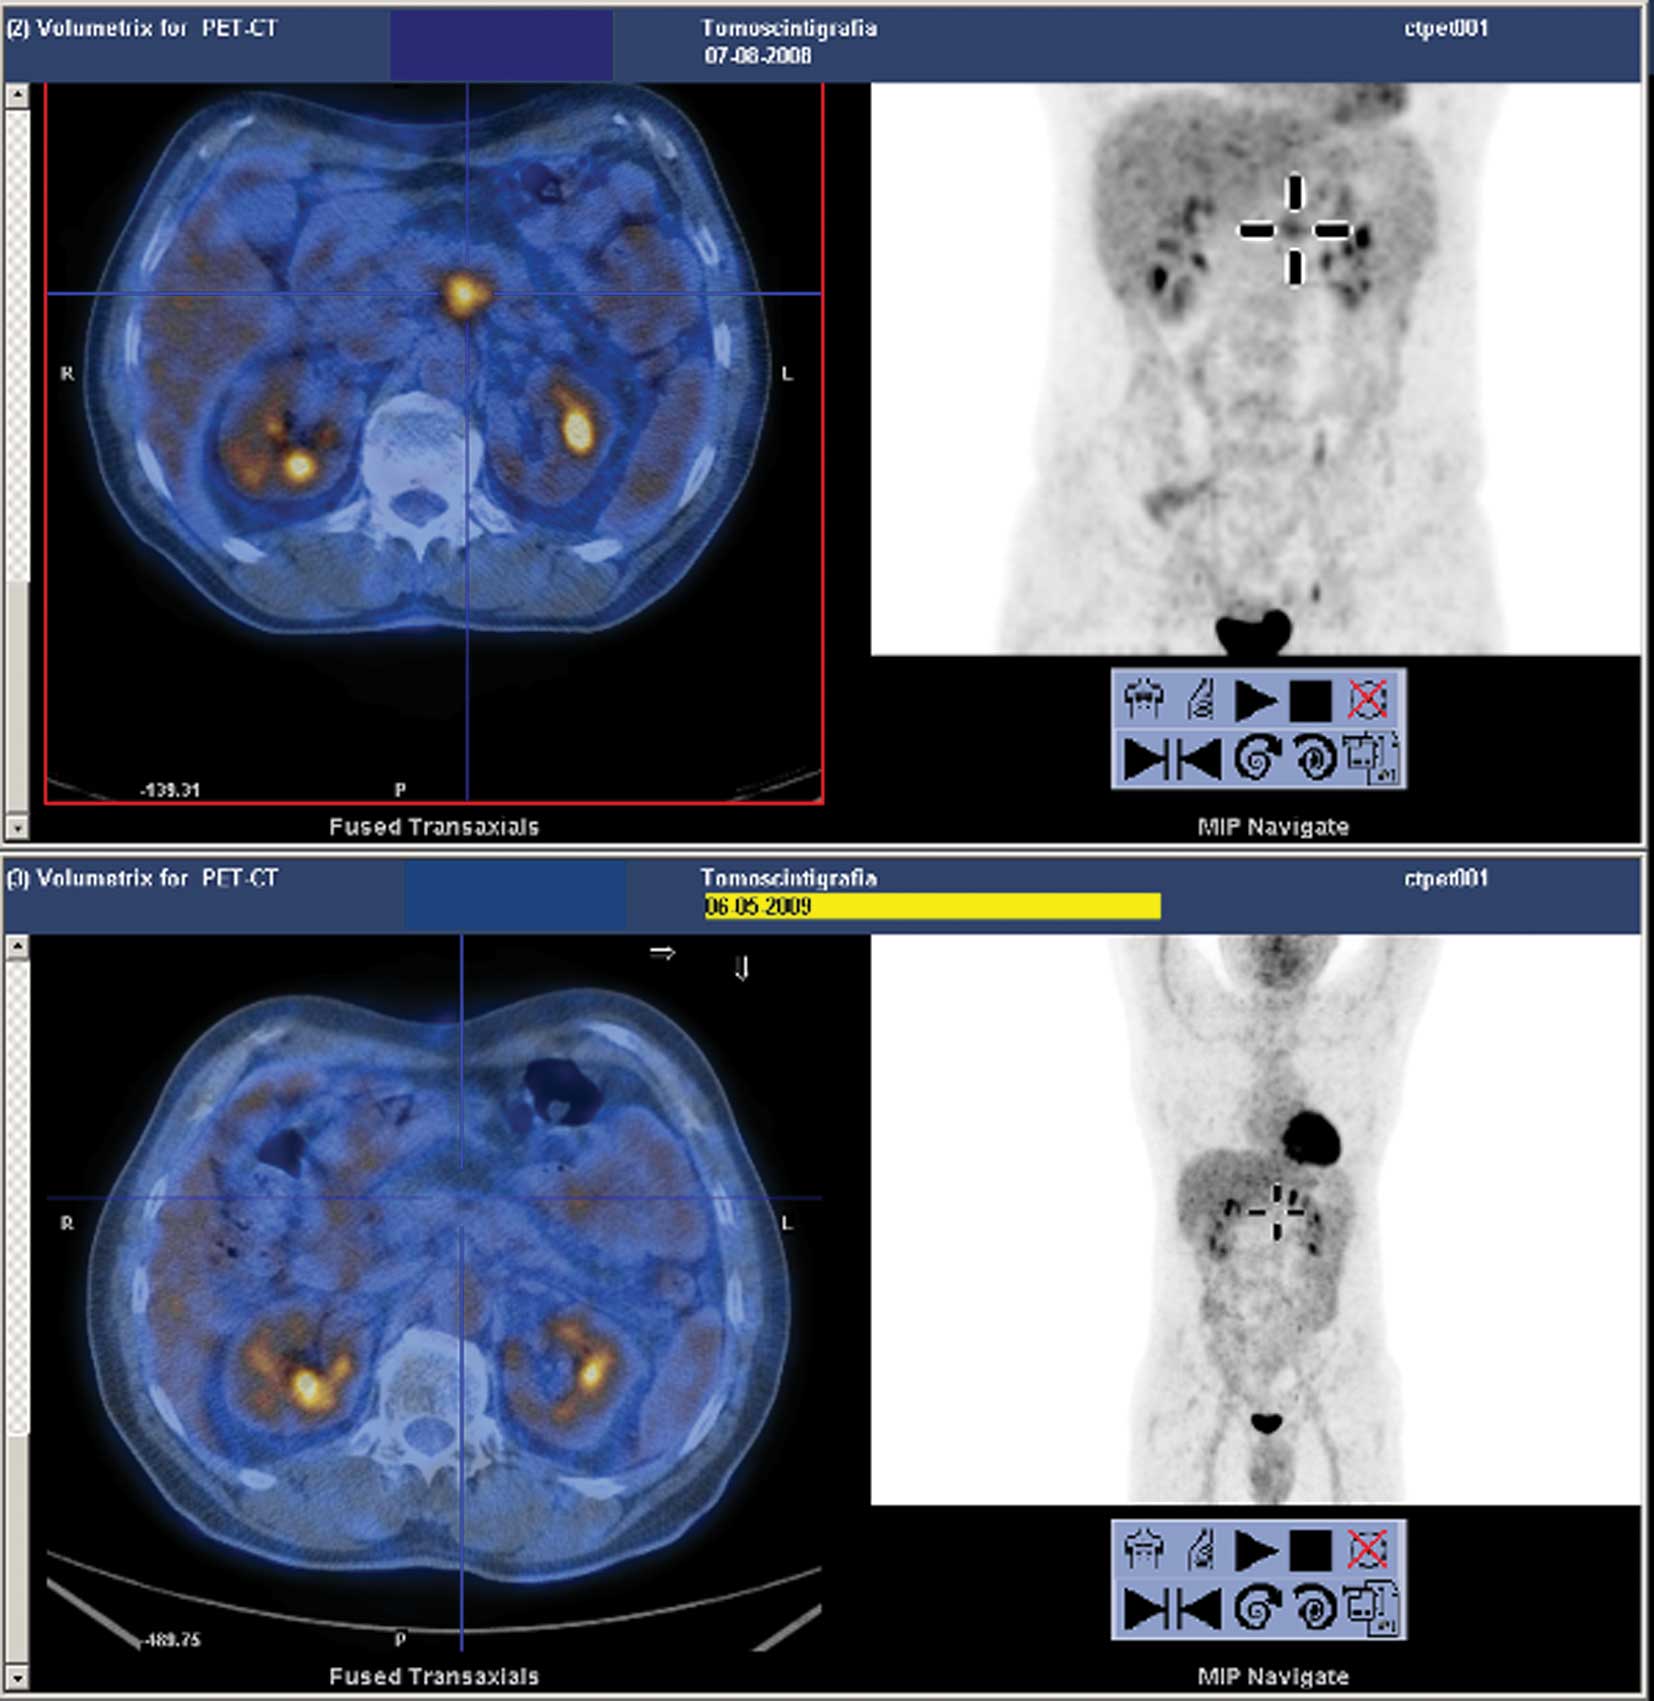

Figure 1

18CT-PET evaluation prior to and following chemoradiotherapy treatment in patient 1.

In August 2008, a 63-year-old male was diagnosed with locally advanced stage and poorly differentiated carcinoma originating from the head of the pancreas. The Eastern Cooperative Oncology Group (ECOG) performance status was 2. The tumour markers [carcinoembryonic antigen (CEA) and CA19.9] were negative. Since the patient was considered unfit for surgery, the tumour was treated medically. A sequential CHT followed by CRT was scheduled in September 2008. However, the treatment was discontinued due to toxicity, in the form of fever and nausea, during the induction CHT period. In February 2009, an abdominal computed tomography (CT) scan showed a significant reduction of the pancreatic tumour mass and a fluorodeoxyglucose positron-emission tomography/CT (18CT-PET) revealed a complete metabolic response (Fig. 1). Consequently, the patient underwent surgery. Since the tumour involved the coeliac axis and superior mesenteric artery, surgery was confined to explorative laparotomy. In July 2009, a CT scan showed a further reduction of tumour size, and 18CT-PET confirmed the complete metabolic response. The ECOG performance status was 0. In agreement with the patient, treatment involved the maintenance of GEM at 1000 mg/mq on days 1, 8 and 15 of a 28-day cycle from July 2009 to February 2010, when a single hepatic metastasis developed, 18 months following the LAPC diagnosis. A slight increase in CEA was found (6.7 ng/ml). Thus, CHT with gemcitabine and oxaliplatin (GEMOX schedule) commenced from March 2010. During treatment, a case of grade 3 neutropenia occurred.

This study evaluated clinical cases of patients characterized by long-term DCR and metabolic tumour deactivation, as noted by a negative 18CT-PET, obtained first by the early sequential CRT schedule, and followed by further treatment modality (Figs. 1 and 2). Patient 1 developed a single hepatic metastasis 18 months after LAPC diagnosis, following upfront sequential CRT and the first line CHT. The patient remained alive at 23 months and in good clinical condition. RFA appeared to prolong disease control in patient 2. This patient developed metastasis 24 months after the LAPC diagnosis. The two patients therefore experienced clinical benefits.

Figure 2

18CT-PET evaluation prior to and following chemoradiotherapy treatment in patient 2.